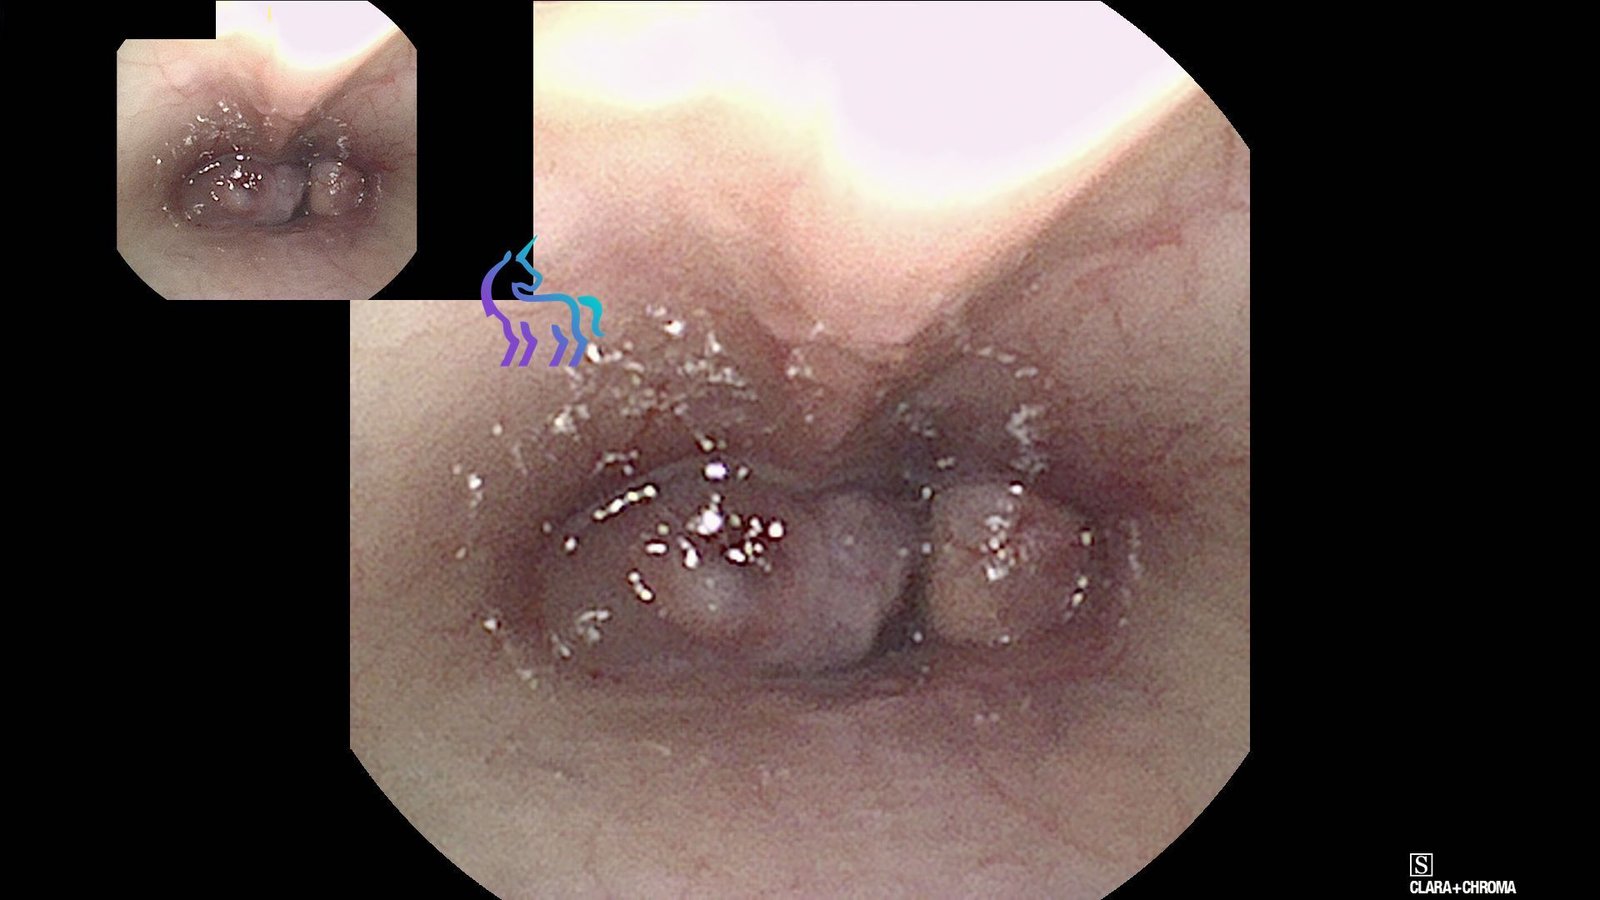

Visualisation d’une masse obstructive au niveau du nasopharynx par voie rétrograde.

Rhinoscopie rétrograde : Masse nasopharyngée

Espèce : ChatLors de la rhinoscopie réalisée par voie rétrograde, une masse occupante a été visualisée au niveau du nasopharynx.

Cet aspect est compatible avec une lésion obstructive majeure, expliquant les signes respiratoires chroniques (jetage, éternuements, gêne inspiratoire). Des prélèvements (biopsies et cytologie) ont été effectués sous contrôle visuel.

Diagnostic retenu : La visualisation précise de la masse permet de confirmer l’obstruction. Les analyses permettront de préciser sa nature (inflammatoire ou tumorale) afin d’orienter la prise en charge thérapeutique.